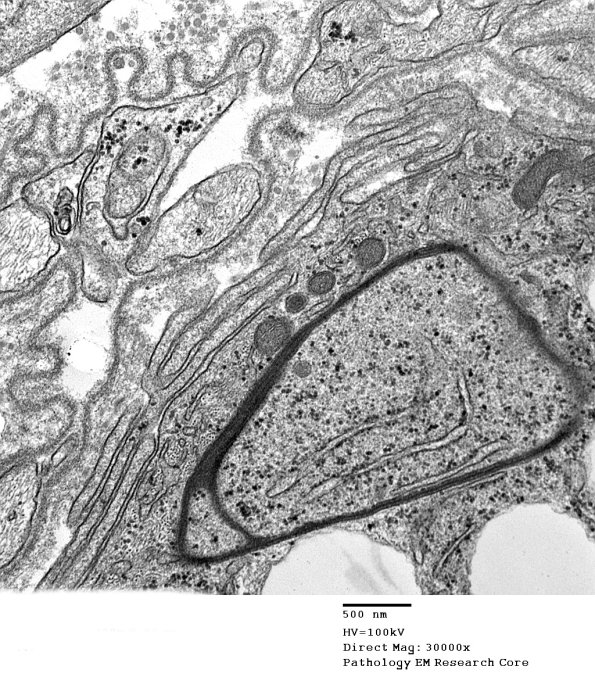

An additional view of the macrophage cytoplasm and the Schwann cell basement membrane.